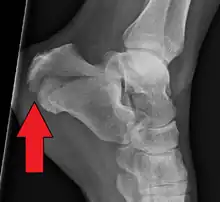

X-ray of a fractured calcaneus

A calcaneal fracture is a break of the calcaneus (heel bone).[1] Symptoms may include pain, bruising, trouble walking, and deformity of the heel.[1] It may be associated with breaks of the hip or back.[1]